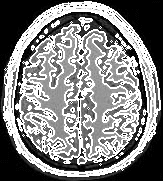

Segmentation of an MRI brain image, using two level set functions to represent the evolving contours